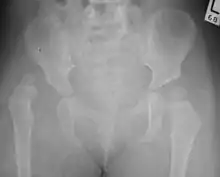

Congenital dislocation of the left hip in an elderly person. Closed arrow marks the acetabulum, open arrow the femoral head. | |